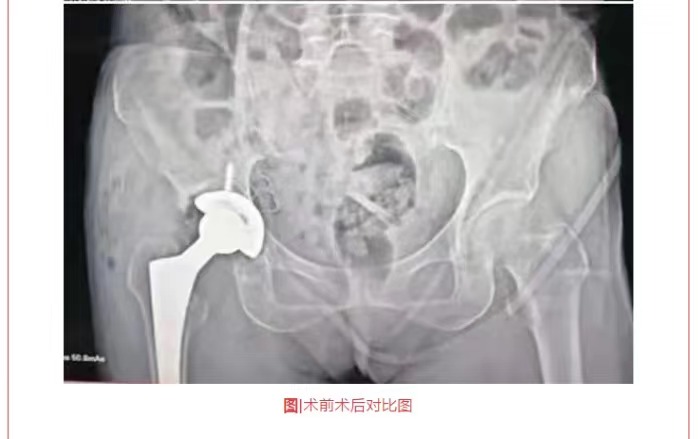

熱烈祝賀穗康長(zhǎng)貞醫(yī)院成功完成兩例全髖關(guān)節(jié)置換術(shù)